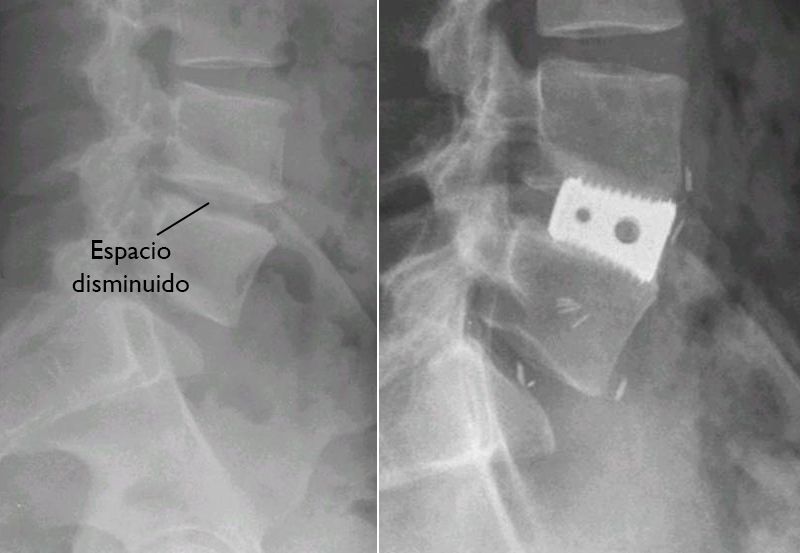

(Izquierda) Esta radiografía de la columna vertebral lumbar muestra el espacio de disco disminuido entre las vértebras. (Derecha) En una fusión intercorporal lumbar anterior (FILA), se ha insertado una jaula metálica para fusión intercorporal para restaurar la altura normal del espacio del disco. El injerto óseo está adentro de la jaula y no se puede observar en la radiografía.